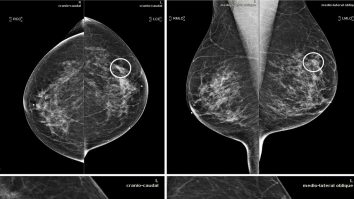

Inteligenţa artificială, folosită pentru tratarea cancerului. Arată ce combinație de medicamente distruge celulele canceroase

Sănătate